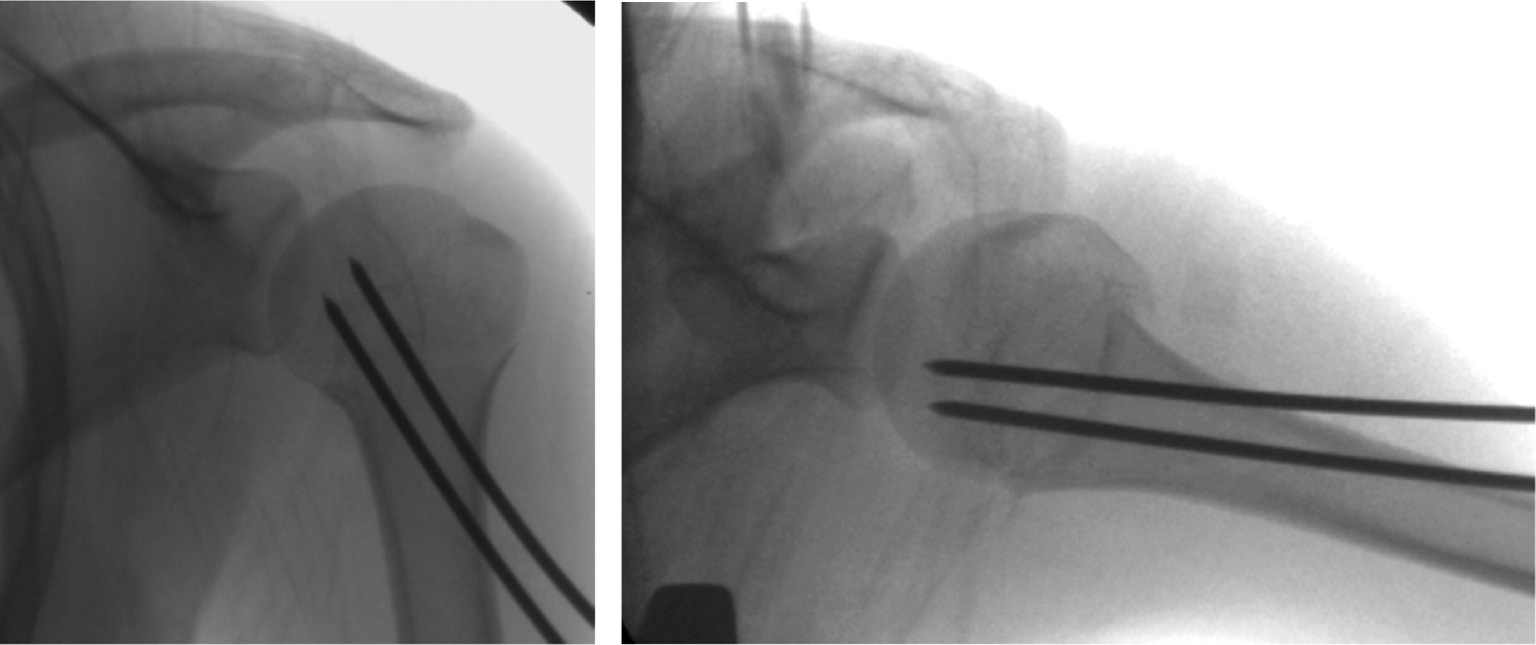

Patients are placed in the modified beach chair position or supine with elevation of the affected shoulder on a radiolucent table. Closed reduction is attempted, frequently prior to prepping the patient, with traction, abduction, and rotation with counter-traction; obtaining appropriate length should be the main focus of the reduction. If this is unsuccessful, open reduction through the deltopectoral approach is performed. Two 2.8-4.0 mm Steinmann pins, threaded or unthreaded, are advanced from lateral to medial across the fracture site and into the humeral epiphysis (Figure 7).

Figure 7. AP and lateral fluoroscopy images of a 16-year-old girl status post closed reduction and percutaneous pinning of a left proximal humerus fracture.

Of note, pins are placed distally to avoid the axillary nerve. Orthogonal views of the proximal humerus to assure proper pin placement and reasonable fracture reduction is paramount; when difficult, an axillary view of the shoulder is most helpful.32 The surgeon may consider burying pins in the proximal humerus.